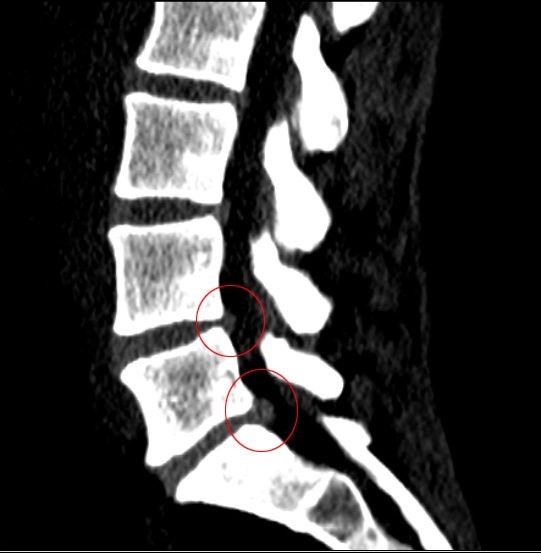

Etirement lombaire pour hernie discale l4 l5 l5 s1. The most common level is at the L5S1 level of the spine The L5 disc is the lumbar disc that is the lowest on the spine and the S1 disc is right below it Voici 9 exercices à faire à la maison pour soigner les douleurs d'hernie discale lombaire ou cervicale N'attendez pas pour soulager vos maux rapidement Étirements Pour Sciatique. 2e visite Scanner lombaire Verdict Hernie discale latérale et foraminale gauche L5S1 compressive sur la racine S1 gauche Pas d'anomalie significative aux autres étages Prescription 15 séances de massage chez le kiné rééducation de la position (ou un truc du genre). Hernie discale lombaire Sciatique cruralgie Hernie discale L5 S1 et L4 L5 Paris Anatomie, traitement médical Chirurgie et microchirurgie Operation.

– Àl’étage L4L5 et L5S1, déshydratation discale sans protrusion significative et sans conflit discoradiculaire Pas de sténose canalaire ou foraminal Zygarthrose modérée lombaire basseIntégrité des articulations sacroiliaques et coxofémorales. Démonstration d'un exercice de décompression lombaire Eldoa L5S1 Duration 140 Axellite Santé Globale Coaching de santé, Ostéopathie, Posturologie 110,677 views 140. Diagnostic de la hernie discale lombaire Toutes les hernies discales lombaires ne sont pas symptomatiques ( à 40 %) En effet, certaines peuvent être découvertes fortuitement lors du bilan radiologique d'une autre pathologie Les examens complémentaires permettent d'authentifier la hernie discale.

GRAVITÉ D’UNE HERNIE DISCALE?. Doctinews N° 90 Juillet 16 C ette pathologie touche essentiellement l'adulte jeune (2545 ans) Le diagnostic précis se fait par une IRM lombaire ou, à défaut, par un scanner lombaire Le traitement de la hernie discale est en premier lieu conservateur par le repos, la physiothérapie et les médicaments. "Les disques les plus touchés sont les plus mobiles, ceux situés en bas de la colonne vertébrale, les disques L4/L5/S1" précise le rhumatologue Causes La discopathie la plus fréquemment rencontrée est la discopathie dégénérative , un processus de détérioration progressive d'un disque intervertébral principalement dû à l'arthrose.

Les radiographies montrent le pincement du disque entre la 4ème et la 5ème vertèbre lombaire (L4/L5) ou la 5ème vertèbre lombaire et la 1ère vertèbre sacrée (L5/S1) Le pincement peut être unilatéral ou remplacé par un baillement postérieur et/ou latéral Parfois les clichés du rachis lombaire sont normaux. Cidessous un dessin représentant trois différents types de hernie discale lombaire On distingue l’anneau fibreux (en bleu) à travers lequel est passé un fragment du noyau discal La sciatique est plus fréquente que la cruralgie, et elle est provoquée par une hernie L4L5 ou L5S1 La chirurgie consiste à retirer la hernie. Regardez Etirement Lombaire pour hernie discale L4L5/L5S1 Cydonia sur Dailymotion Recherche Bibliothèque Se connecter S'inscrire Regarder en plein écran il y a 4 ans 864 vues Etirement Lombaire pour hernie discale L4L5/L5S1 Cydonia Suivre il y a 4 ans 864 vues Signaler Vidéos à découvrir À suivre 1302 Etirement.

Les radiographies montrent le pincement du disque entre la 4ème et la 5ème vertèbre lombaire (L4/L5) ou la 5ème vertèbre lombaire et la 1ère vertèbre sacrée (L5/S1) Le pincement peut être unilatéral ou remplacé par un baillement postérieur et/ou latéral Parfois les clichés du rachis lombaire sont normaux. GRAVITÉ D’UNE HERNIE DISCALE?. Méthode McKenzie étirement #2 pressup Cet exercice consiste à garder le dos cambré afin de diminuer le compression du nerf sciatique provoquée par une her.